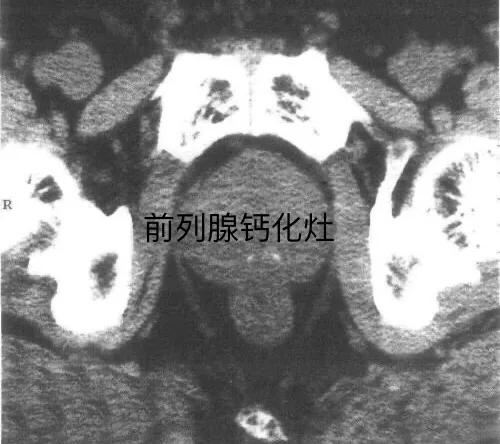

CT检查诊断前列腺钙化灶也比较清楚明确。

前列腺钙化灶需要注意与前列腺肿瘤钙化、结核钙化、膀胱结石、后尿道结石、精囊结石等相鉴别。